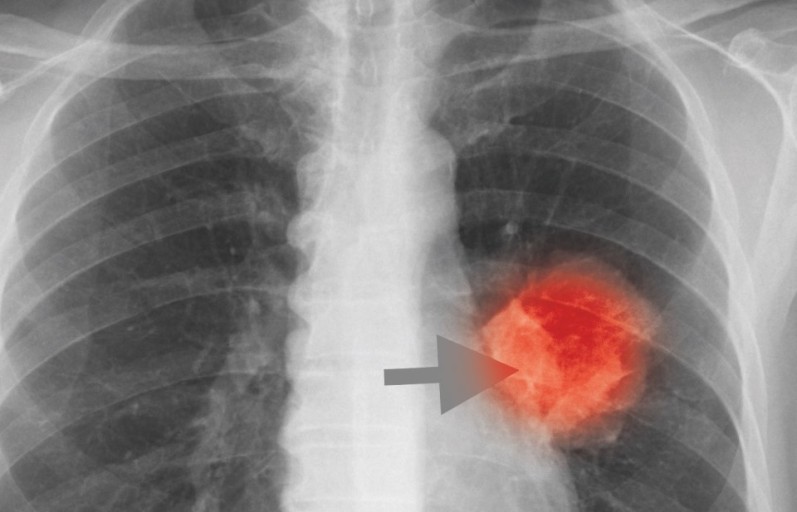

폐암 증상에는 기침, 체중 감소 흉통, 혈담 즉 피가 섞인 가래, 호흡곤란 등이 있지만, 위 증상은 다른 폐 질환에서도 나타날 수 있는 증상으로 구분하기가 어렵다. 그리고 폐암 초기에는 특별한 증상이 없는 경우가 대부분이라서 최근 흡연뿐 아니라 미세먼지 등 여러가지 요인으로 폐암이 발생하는 경우가 많아 정기검진으로 조기에 발견하는 것이 중요며 폐암 검진을 위해서는 특히나 저선량 흉부 CT를 촬영하는 것이 좋다라고 전문가들은 말하고 있습니다..

보통 숨소리는 크게 들리지 않지만, 목이나 폐 부분에 뭐가 걸린 느낌이 나듯이 숨소리가 거칠어지는 걸 느낍니다.면 폐에 문제가 생겼을 확률이 높다. 꼭 내원해 엑스레이를 촬영해 보는 게 바람직합니다..